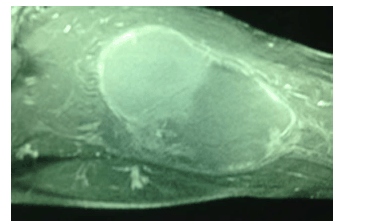

A imagem a seguir, de uma RNM da coxa direita, representa uma massa de crescimento rápido no grupo muscular posterior de um paciente do sexo masculino, negro, com lesões umbilicadas em tronco e membros superiores e inferiores. Chama a atenção a presença de uma mancha do tipo “café com leite”no ombro esquerdo. A biópsia incisional dessa lesão revelou “neoplasia fusiforme de padrão sarcomatóide; provavelmente se trata de um rabdomiossarcoma“.